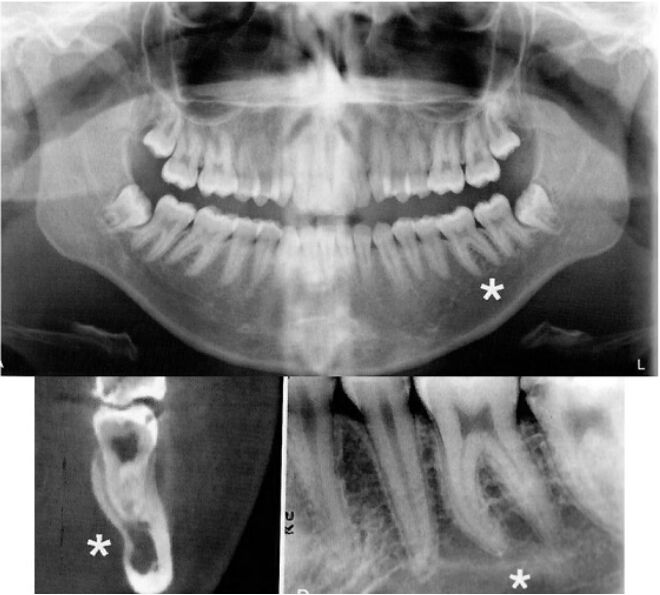

65.附圖X光影像中,星號所指之放射線透過性區域為何? (A)顎下窩(submandibular fossa) (B)創傷性骨囊腫(traumatic bone cyst) (C)單純性骨囊腫(simple bone cyst) (D)骨質疏鬆症(osteoporosis)

67.病人左下第二小臼齒處腫脹疼痛,X光檢查結果如圖,其左下第二小臼齒有何形態異常? (A)第一型牙本質發育不良(dentin dysplasia type I) (B)雙生齒(gemination) (C)齒中齒(dens invaginatus) (D)齒外齒(dens evaginatus)